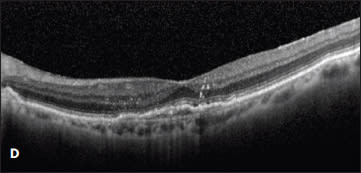

Figure 5. A patient with a serous PED was observed at presentation (A) and developed subretinal fluid three months later (B). Treatment was offered at three months, but the patient declined until a PED developed in the fellow eye 13 months later (C). At that time, the patient underwent intravitreal treatment with bevacizumab, with resolution of the subretinal fluid and a decrease in height of the PED (D). The patient’s vision was 20/32 both before and after treatment.

Case 5. The desire to avoid the risk of an RPE tear led one patient to refuse anti-VEGF therapy for more than a year and a half. This 69-year-old man presented with a large serous PED in the right eye, resulting in decreased vision from 20/20 to 20/126 (Figure 5A). There was no associated intraretinal or subretinal fluid on OCT, and due to the ability to correct his vision comfortably with a hyperopic refraction, observation with close follow-up was chosen.

Three months later, his vision remained 20/32, but subretinal fluid was noted on OCT (Figure 5B). Treatment was recommended, but the patient refused therapy. On multiple return visits, the patient continued to decline treatment. Sixteen months after his initial presentation, he developed metamorphopsia in his left eye, and a new serous PED was seen on OCT. The PED in his right eye had a stable cuff of subretinal fluid (Figure 5C).

At this point the patient consented to treatment with intravitreal bevacizumab in the right eye. After three injections, the subretinal fluid resolved, and the PED decreased slightly in apical height (Figure 5D). His vision remained unchanged at 20/32 throughout treatment.